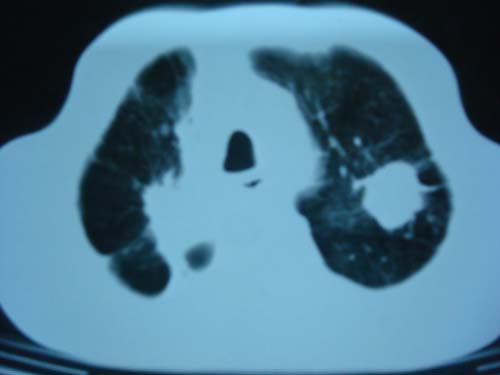

病灶有分叶,毛刺,考虑肺癌可能性大,建议穿刺。

病灶有分叶 毛刺 左侧叶裂上移 考虑肺癌可能性大 建议穿刺

右上肺结核,左上肺周围型肺癌可能性大

团块状病灶,病灶周围长毛刺及灶周肺气肿。